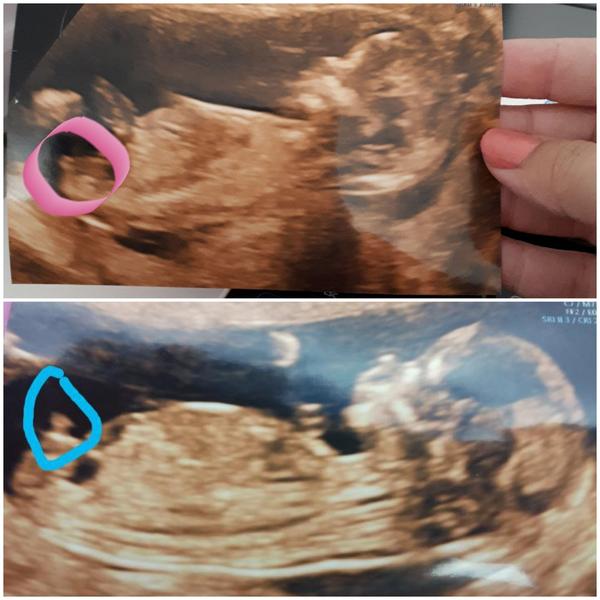

A kdyz se nezeptas,nereknou nic tuplem 😉 ja se u druheho mimca ptala uz na 1. a jen tak naznacila,ze by to mohl byt kluk ale ze je brzo. Na kontrole na gynde mi to pak ale dle smeru toho hrbolku rekla taky,ale ze jinak si to schovava. A pozdeji se kluk potvrdil.

@elsy3 podle pohlavního hrbolku který jde krásně vidět za mě holčička